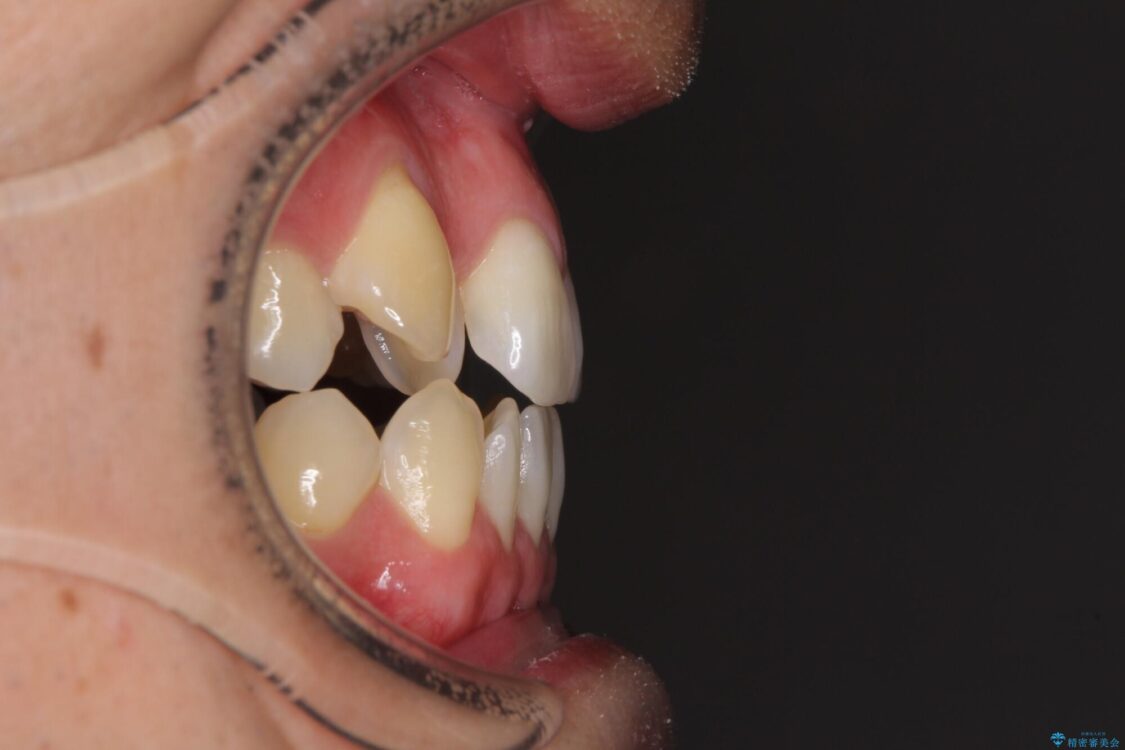

八重歯と前歯のデコボコを気にして来院された患者様です。

治療前

• 左右の八重歯が気になる ワイヤー装置での咬み合わせ改善 治療前画像